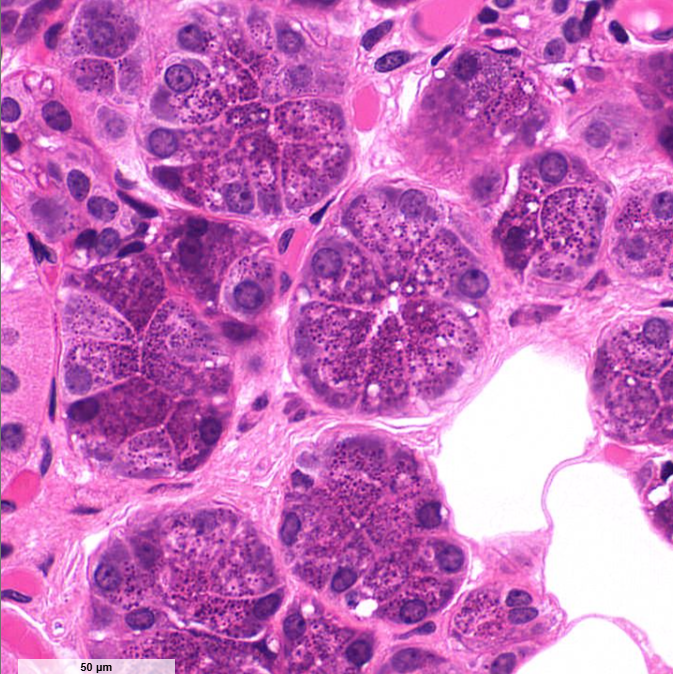

exocrine cells of the pancreas

secrete insulin and glucagon

shaped like a slice of pie

structure

islet of Langerhans of the pancreas

endocrine cell

secrete hormones for digestion